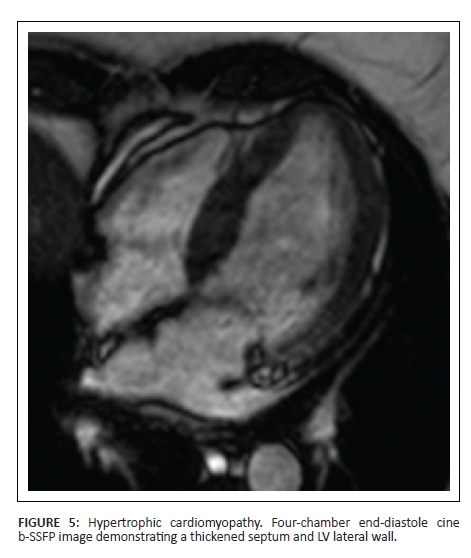

HCM is the most common genetic cardiomyopathy, with an incidence of 1 in 500. It is also the most common cause of sudden death in the young, including athletes. Clinical findings and abnormal ECG findings associated with apical or asymmetrical septal hypertrophy, with or without dynamic LV outflow tract obstruction, is diagnostic. Pathologically, HCM demonstrates myocyte hypertrophy, disarray and fibrosis, manifesting in various genetic mutations.1 The majority of individuals carrying an HCM genetic defect do not manifest the clinical expression at all times of their lives. Hence an unexplained mildly thickened LV wall may be consistent with a HCM-causing mutation. Making a diagnosis of HCM can be complicated in patients with aortic stenosis or hypertension.1

Cine images allow the detection of LV wall thickness, especially at the apex, basal anteroseptal wall and posterolateral wall - regions that are difficult to visualise on echocardiography. However, a spectrum of LV wall thickening has been described.21 Myocardial crypts are additional typical findings. Apical aneurysms are associated with an increased risk for arrhythmia, thromboembolic events and progressive heart failure.22

LGE is present in 80% of HCM, both patchy or diffuse scarring, the latter in areas of increased thickness typically and less commonly in regions of normal wall thickness.23 Patchy LGE is typically midwall in thickened myocardium and commonly the RV-LV insertion points are also involved. In burnt-out HCM, the myocardium is thinned and has transmural LGE, mimicking ischaemic disease, but not in a coronary artery territory.

HCM without LGE has 100% event-free survival at 6-year follow-up; LGE > 5% of LV mass, septal wall thickness > 30 mm and AF are independent predictors of death and ICD discharges.24

Figure 5 and Figure 6 demonstrate the imaging features of HCM.